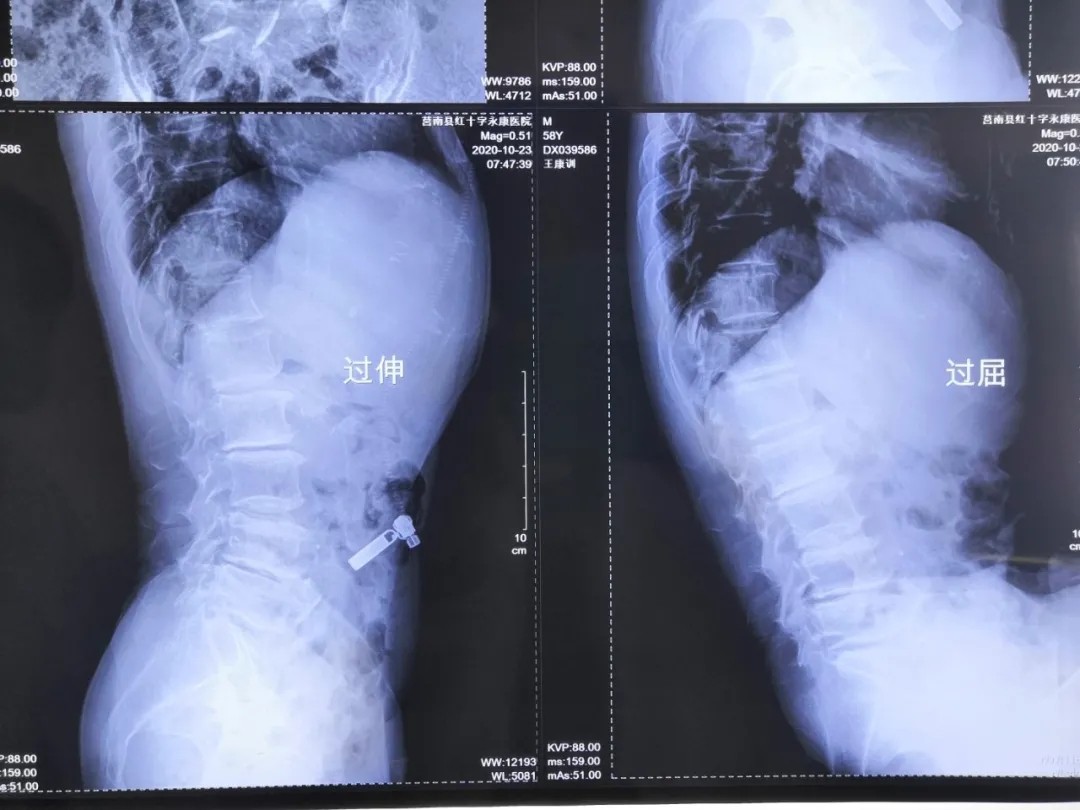

患 者:男,58岁。

主 诉:右下肢放射性疼痛1个月,加重5天。

现病史:患者慢性腰腿痛病史10年,间断发作,多次在当地医院行保守治疗,近1个月疼痛加重,以右下肢放射痛为主,右小腿前外侧为重,不能行走,影响睡眠。

查 体:双侧直腿抬高试验阴性,右小腿前外侧、右足拇指背侧感觉减退,右足拇指背伸肌力3级,右下肢股四头肌肌力4级,左下肢肌力5级。VAS评分9分

影像资料:

诊 断:

腰椎管狭窄症;腰椎间盘突出症;老年退变性侧弯。